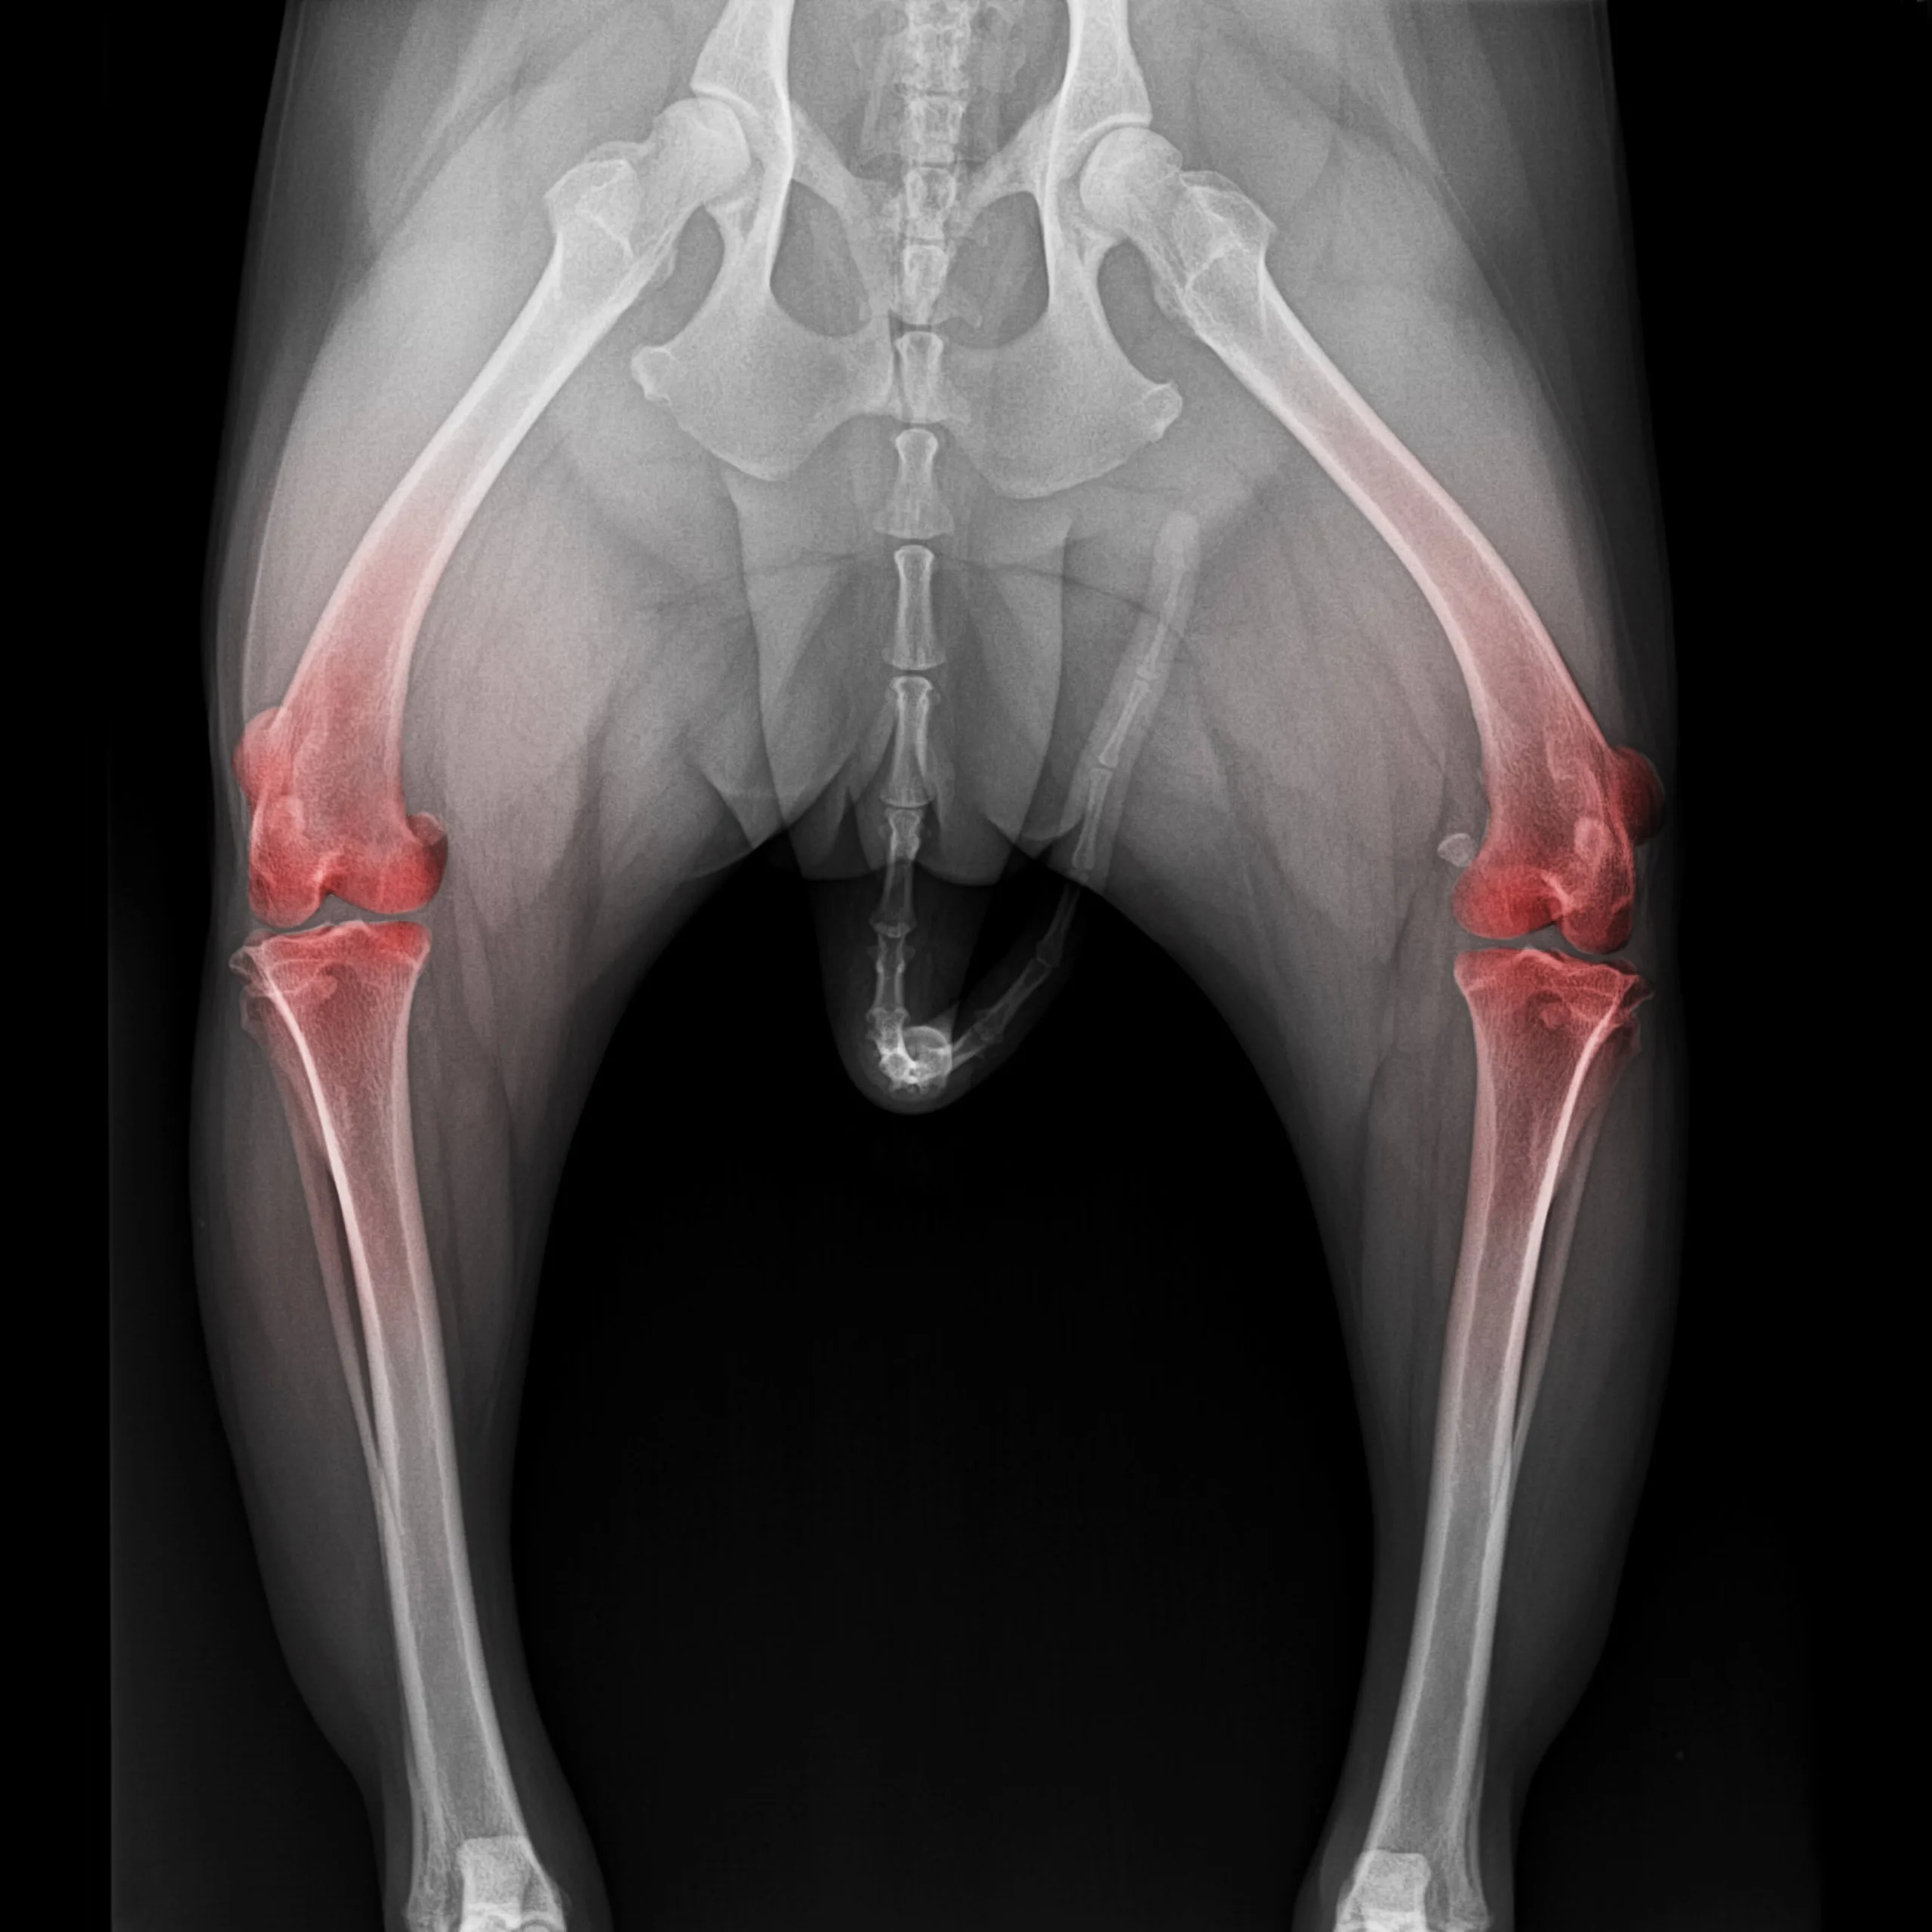

The growth plates are still open in this puppy

A food specially designed for puppies is perfect for the healthy growth and development of bones and joints. Bones grow from growth plates found at the end of long bones, and when these growth plates close, the dog is considered fully developed. This closure may occur at around 9-12 months for small breeds, but it may not happen until the dog is 18-24 months old in large puppies.

This means that what a puppy eats at this life stage can affect them for their whole life due to its impact on their development. In fact, many orthopaedic problems that show up in adulthood actually develop during the rapid growth phase when the dog is a puppy. While this can be due to over-exercise, some vital dietary factors can increase the risk of skeletal disorders, especially in larger breed dogs.